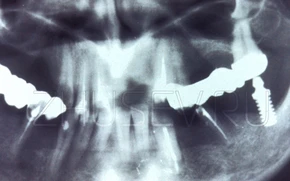

Пластиночный имплантат. Именно этот тип имплантатов был широко распространен в нашей стране с конца 80-х до середины 90-х годов прошлого века.

Абсолютно кустарный, пластиночный имплантат. На нем даже видны следы механической обработки.

Ручная модификация имплантата фабричного производства.

Пластиночные имплантаты очень часто подпиливали или меняли их конфигурацию непосредственно в момент операции.

Еще один вариант пластиночного имплантата.